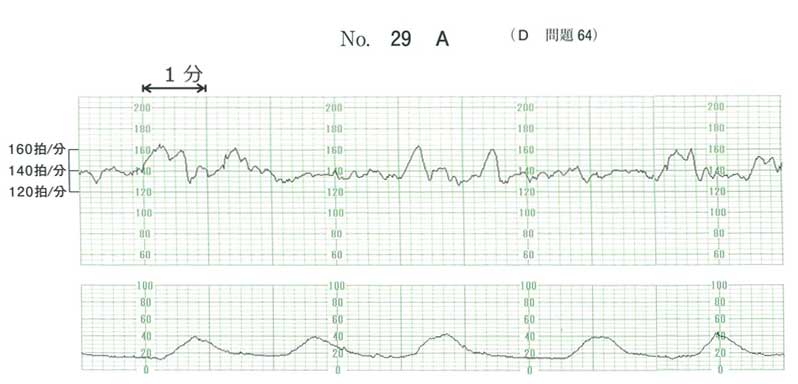

| タイトル:113D-64 | コメント数:5 | 割問 |

ACにしました

淡血性の帯下から感染による子宮収縮をうたがい抗菌薬。

32週で成長も問題ないのでステロイドによる臓器成熟はいらないかと思いましたが、微妙ですね…

cとe

抗菌薬を投与する理由がないと思いました

c,e

A 感染なし×

BDは論外、子宮収縮は来ているのでCは絶対やる

残るはAとEだけど、まぁ抗生剤は行って悪いものではない。

32週、、、微妙なところだけど子宮口は閉鎖しているからすぐに生まれそうな感じではない。少なくともあと2週間は持ちそう。

ということでAC